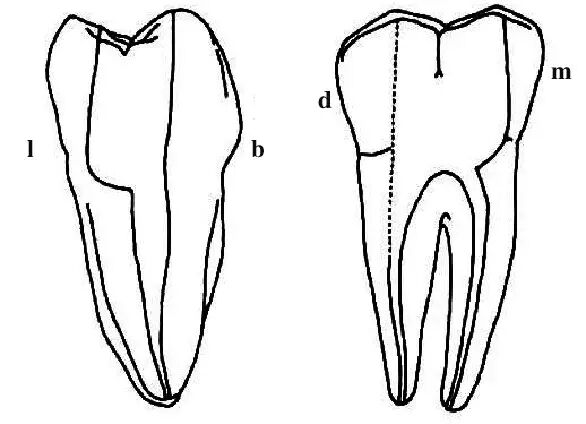

2.根管在x线片上是一种2维的图像,所以虽然有时片子上表现为直的,但事实上根管是一个三维的空间,显示没有近远中向的弯曲,却可能向颊舌向弯曲,这种颊舌向弯曲的信息是平常临床上无法获得的。所以很少有完全直的根管。几乎所有的根管都有一定程度的弯曲.尤其在根尖部。最后这句话几乎可以当作一个定理。我们看下面一张关于根尖孔的图。

a. 根尖孔开口于正常根尖顶部 (56.53%)

b. 根尖孔开口于牙根尖的唇或舌侧

c. 根尖孔开口于牙根尖的近中或远中面

正常情况下根尖孔开口于根尖顶部(图a),这是我们工作中最常见到的影像,但这种情况只有 56.53%,所以还有将近一半的情况是其他的开口形式。图b就表明根尖孔的开口在唇舌向,当我们见到这样的根尖片的时候,要引起足够的重视,有一个特殊的这种情况就是下第二磨牙“C”型根管的术后影像,常会有这样的表现。这种研究国外并没有做的很到位,因为他们很少遇到这种牙齿,到是黄种人的下7常见这种影像,国内还是武汉研究的比较多。以后的内容会有相关的讨论。

图3表明的内容在这种示意图上比较好懂,但临床工作中,有医生容易以为是自己侧穿了,或者其他的什么情况,当然根尖片拍的好坏也很有关系。